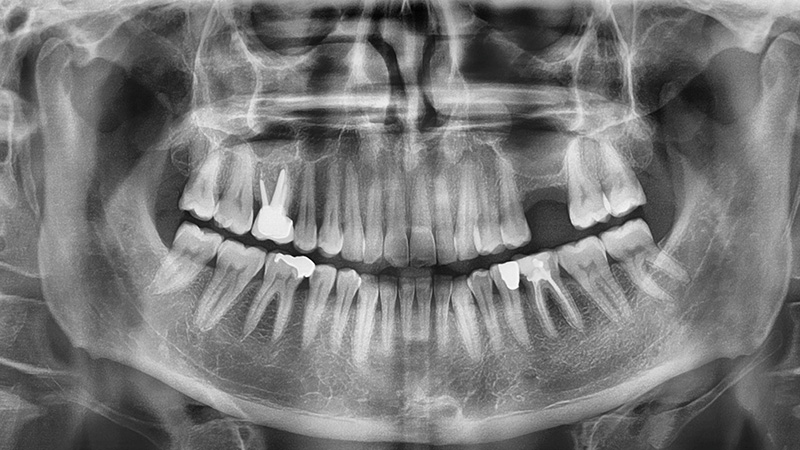

Le sinus radiologique dans tous ses états !

En haut à droite : Sinus sain avec un meat moyen perméable qui permettra le drainage du sinus.

En haut au milieu : Sinus présentant un kyste sous-muqueux.

En haut à gauche : Sinus présentant une Concha bullosa.

En bas à gauche : Sinusite chronique unilatérale.

En bas au milieu : Corps étranger (exemple : pâte endodontique).

En bas à droite : Sinusite par CBS.

Le radio panoramique n’est pas recommandée pour dépister une pathologie du sinus maxillaire, il faut donc s’orienter sur un CBCT et avoir l’ensemble du sinus naso-sinusien.